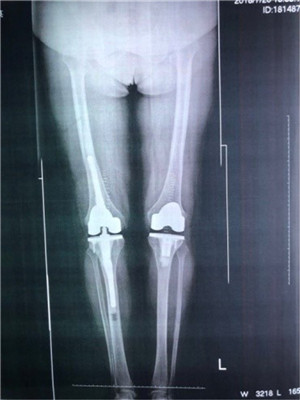

經(jīng)過嚴(yán)密的術(shù)前準(zhǔn)備,6月29日,由張主任親自主刀,在張浩、裴海波、梁求真醫(yī)師的配合下,對(duì)覃阿姨實(shí)施了左膝關(guān)節(jié)置換手術(shù)。由于術(shù)前手術(shù)方案準(zhǔn)備完善,手術(shù)中可能出現(xiàn)的情況都基本得到了解決,患者出血較少,骨科利用PS假體順利地完成了這一高難度膝關(guān)節(jié)外翻置換手術(shù)。7月12日,張主任再次主刀對(duì)覃阿姨實(shí)施了右膝關(guān)節(jié)置換手術(shù)。手術(shù)中,發(fā)現(xiàn)與之前3D打印模型相同,和手術(shù)前的模擬截骨手術(shù)的情況也基本一致。張主任隨即對(duì)覃阿姨進(jìn)行了常規(guī)截骨手術(shù),整個(gè)手術(shù)過程十分順利。第二天,覃阿姨就可以在家人的攙扶下慢慢的下床活動(dòng)了,她和家人總算松了一口氣。一周后,覃阿姨出院時(shí),她已經(jīng)可以使用助步器獨(dú)自行走了。對(duì)此,覃阿姨非常興奮,她說:“這十幾年我都靠著輪椅生活,真沒想到有一天我還能自己站起來走路,這下就不需要家里專門有人陪著我,我還能給他們幫幫忙呢”。

膝關(guān)節(jié)置換術(shù)前術(shù)后對(duì)比